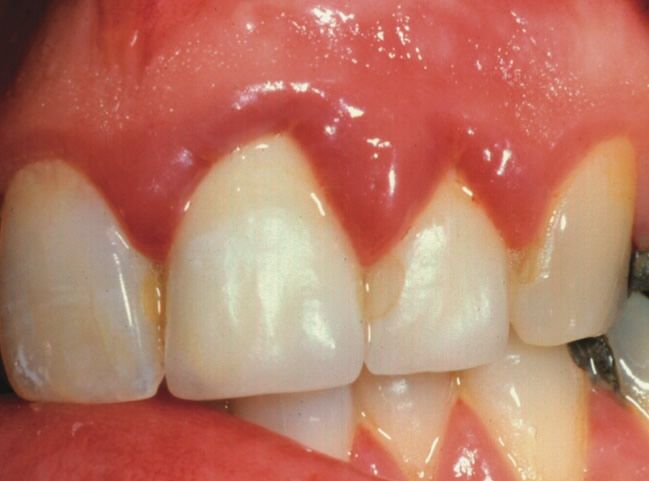

Diş eti şişmesi problemi yalnızca bir dişte oluşabileceği gibi aynı zamanda birkaç diş ve hatta ağız içi tüm dişlerde birlikte görülebilmektedir. Pembe renkli bir doku olan diş eti dişin etrafından başlayarak diş araları ve dişi sarmaktadır. Çoğu zaman diş etleri mikroorganizmalarca iltihabi bir yapı ile kaplanabilmektedir. Söz konusu mikroorganizmalar birçok yolla diş etlerine yerleşebilmektedirler. Yerleştikleri bölgelerde ise renk değişikliklerine, çiğneme yüzeylerine doğru şişmelere ve iltihaba sebep olurlar. [caption id="attachment_3799" align="alignleft" width="401"]

diş eti şişmesi[/caption]

Diş eti şişmesi belirtileri en yaygın olarak çiğneme yüzeyine doğru oluşan büyümeler, kanamalar ve ağrılardır. Diş etinin renginde koyu kırmızı ve maviye dönük kırmızı gibi farklılıklarda gözlemlenebilmektedir. Bazen söz konusu değişimler uzun sürede gelişirken bazen çok hızlı gelişim gösterebilmektedir.